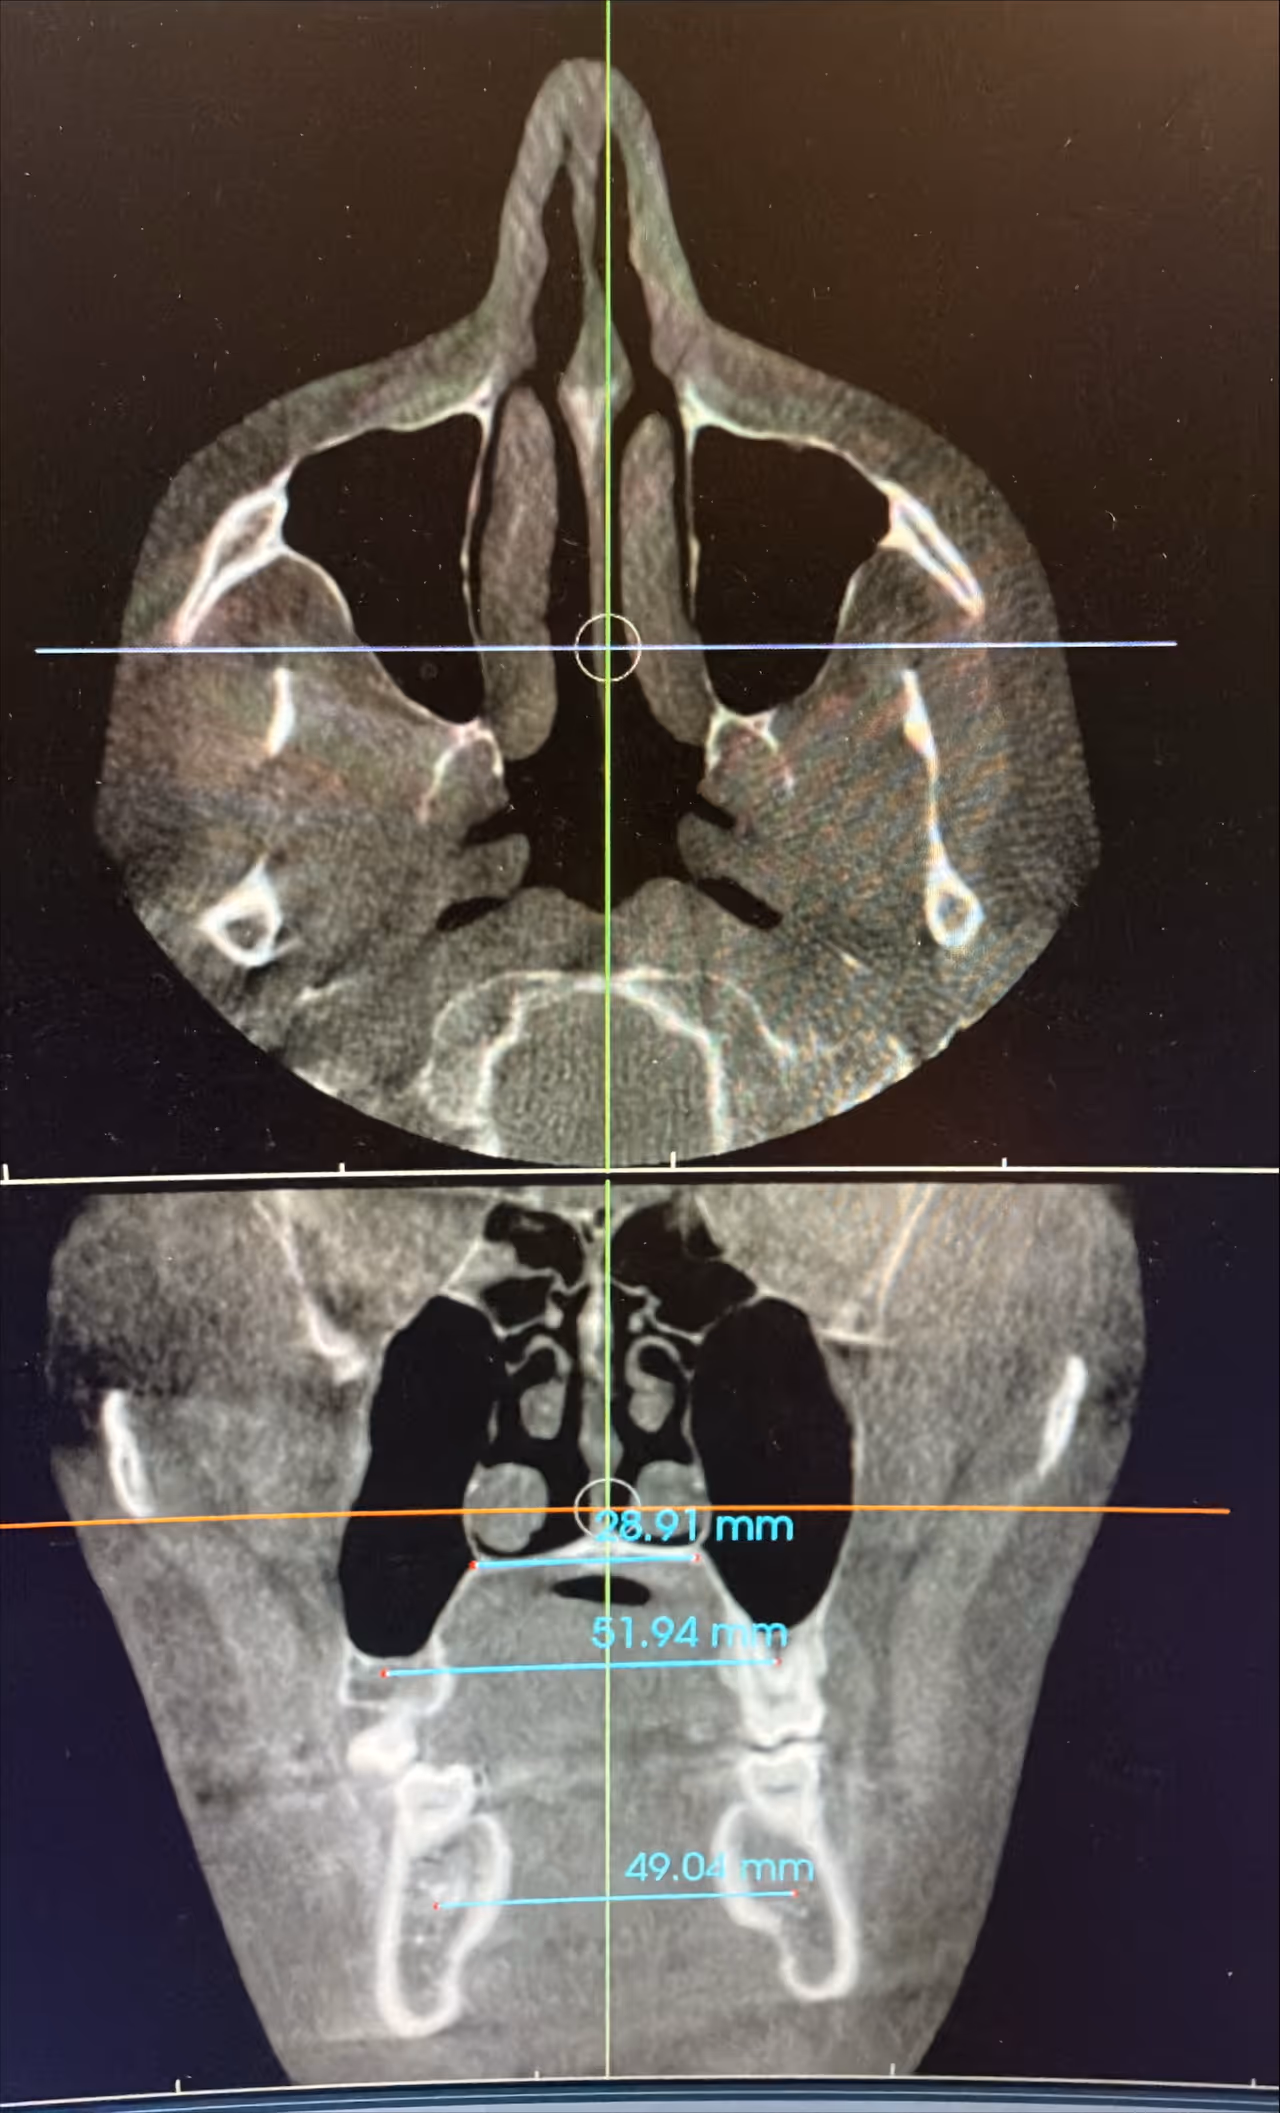

CBCT 3D Imaging

Full visualization of the nasal cavity, jaw, midface, and airway volume in high resolution.

Facial Growth & Skeletal Structure

We evaluate midface width, jaw position, and overall growth direction to determine how the airway is affected by bone development, especially in children.